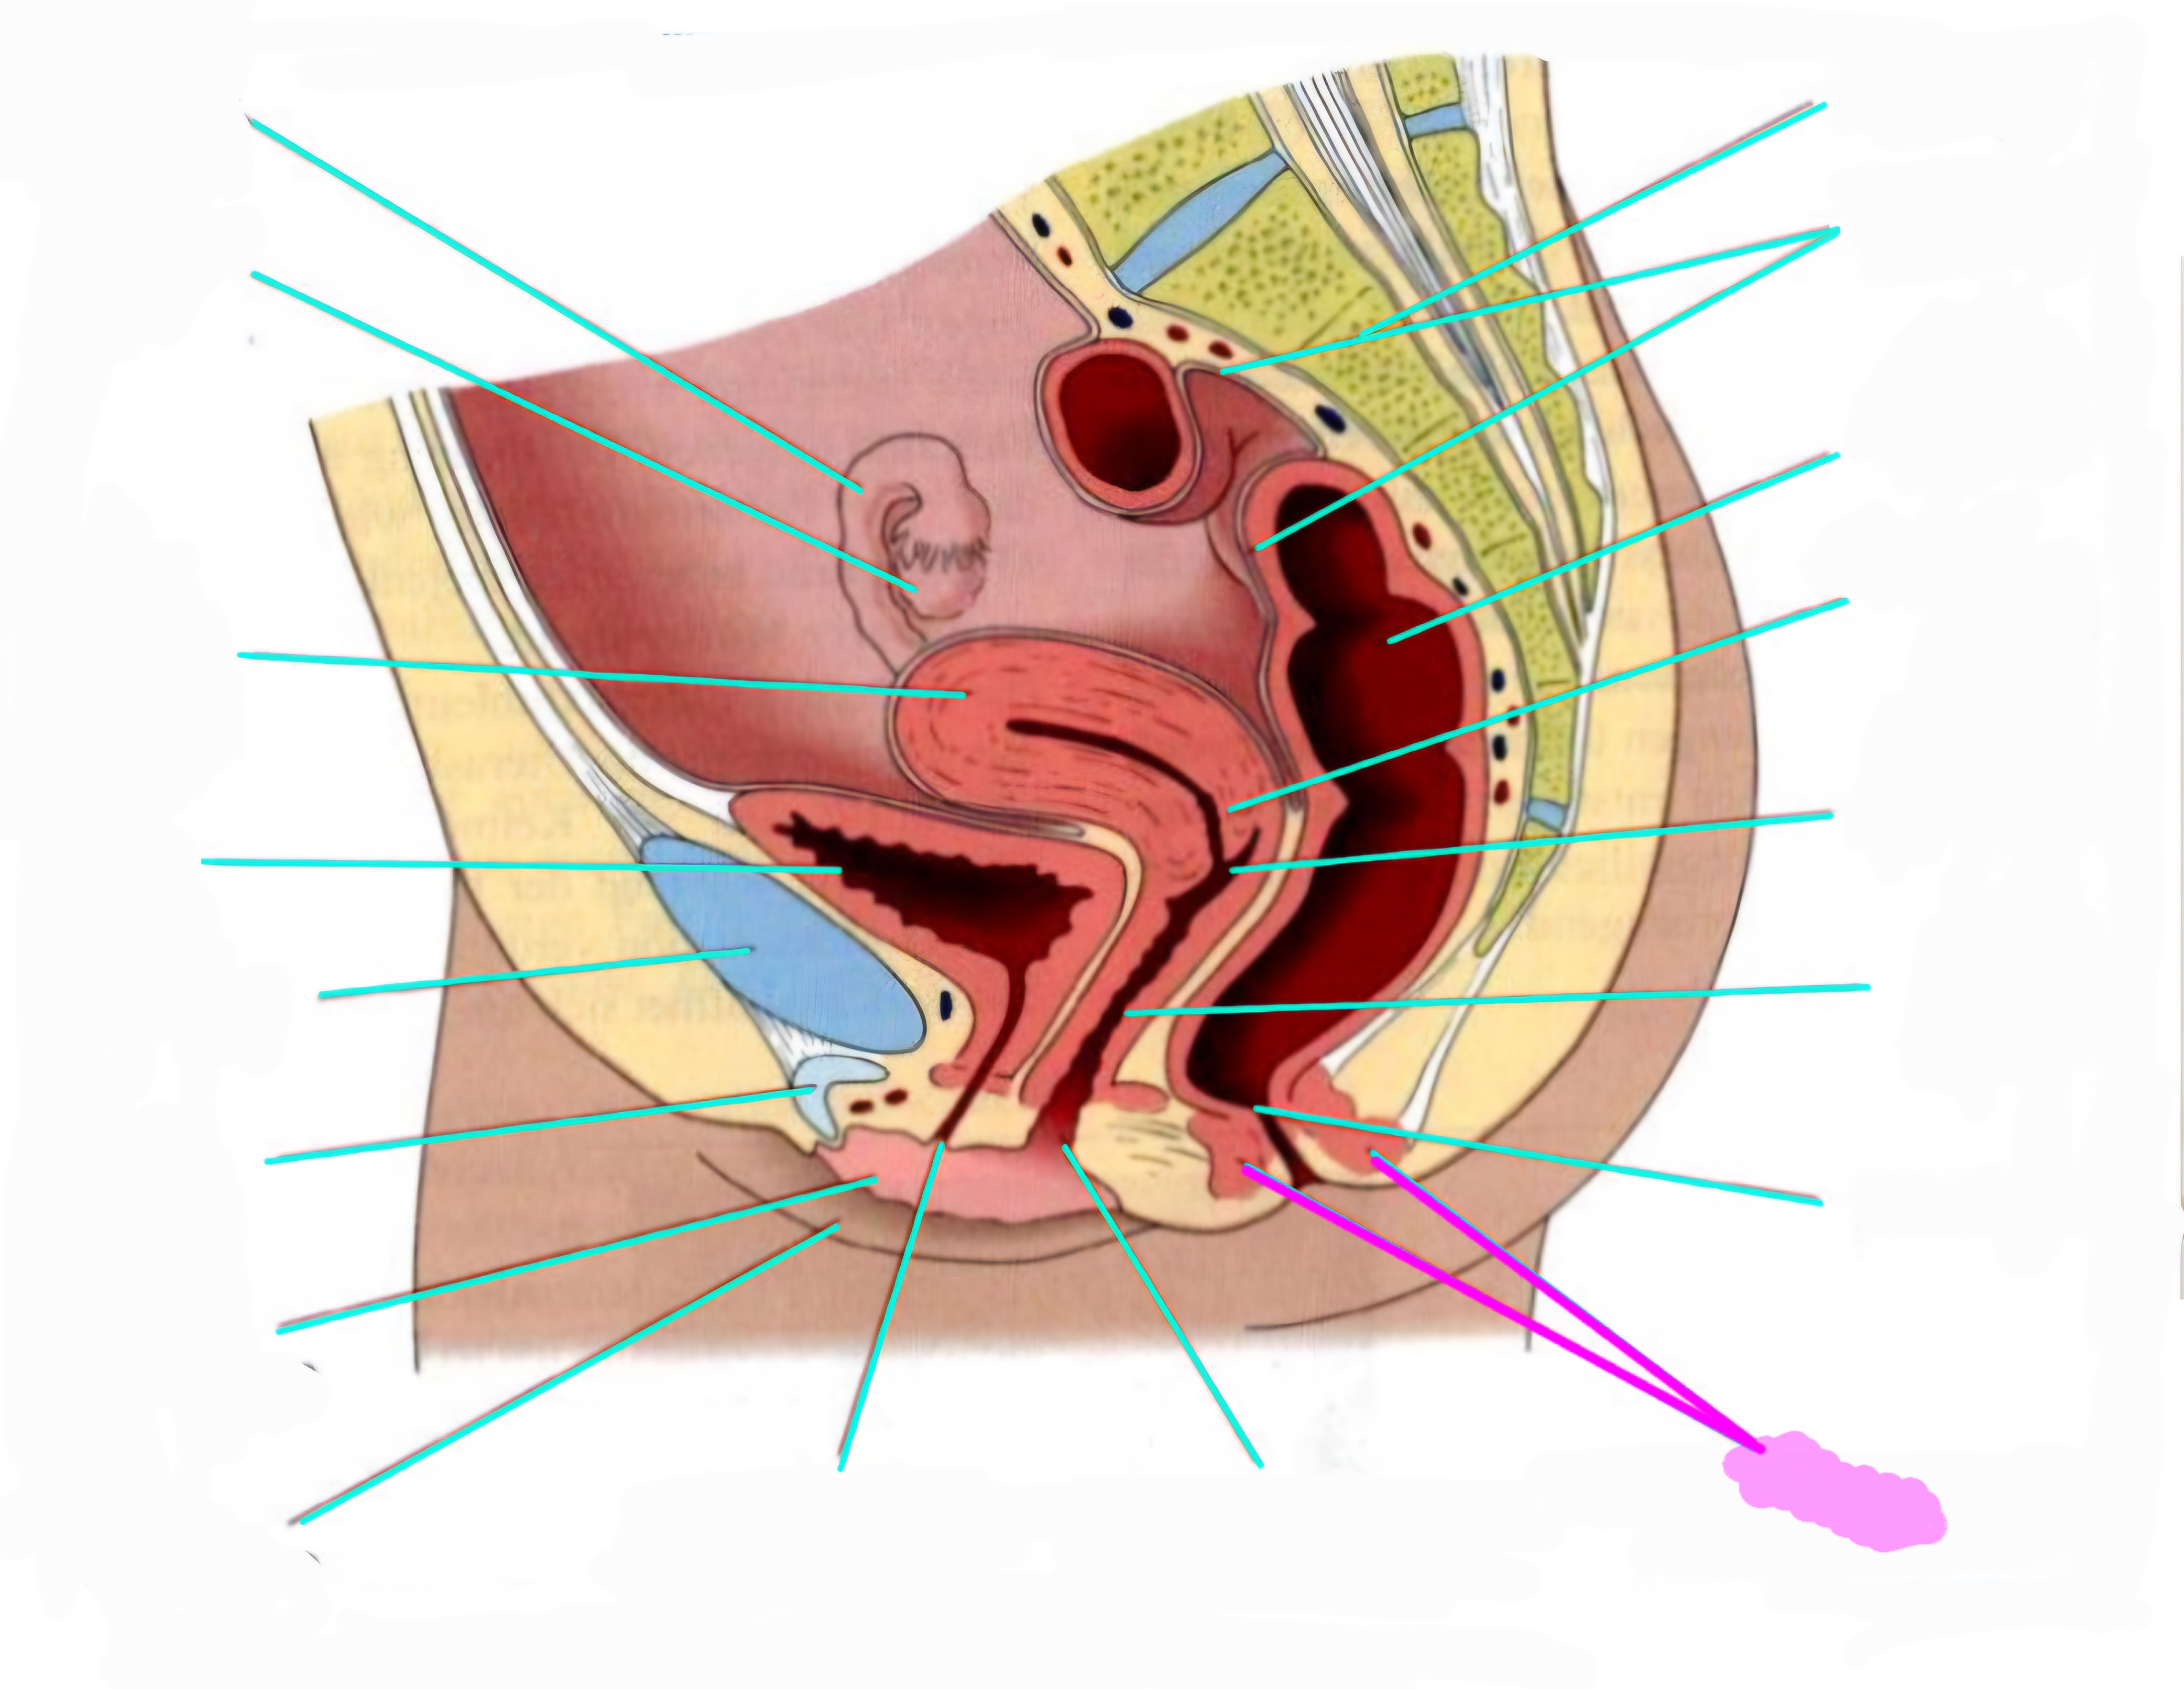

wbl. genital Anatomie

19 Terms

Tubea uterina (Eileiter)

Ovar (Eierstock)

Uterus (Gebärmutter)

Vesica Urinaria (Harnblase)

Symphyse

Klitoris

Labia minor pudendi (kleine schamlippen)

Labia Majoran pudendi (große Schamlippe)

Urethra (Harnröhre)

Introitus vaginae (Scheideneingang)

Sphincter ani externes (äußere Afterschließmuskel)

Anus (After)

Vagina (Scheide)

Portio (äußerer Muttermund)

Rektum (Mastdarm)

Zervix (Gebärmutterhals)

Peritoneum (Bauchfell)

Os sacrum (Kreuzbein)